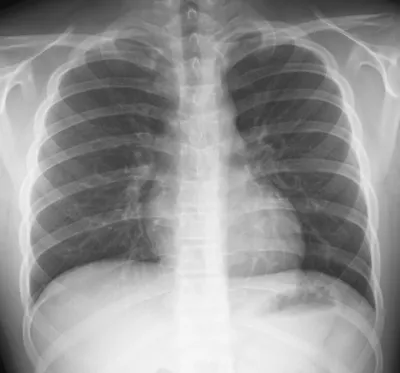

- Permet d'analyser le parenchyme pulmonaire à la recherche notamment d'une pneumonie ou de nodules.

- Permet d'analyser la plèvre à la recherche d'un épanchement ou d'un pneumothorax.

- Permet d'analyser le médiastin à la recherche d'une cardiomégalie ou de ganglions hilaires.

- Permet d'analyser le gril costal à la recherche d'une fracture.